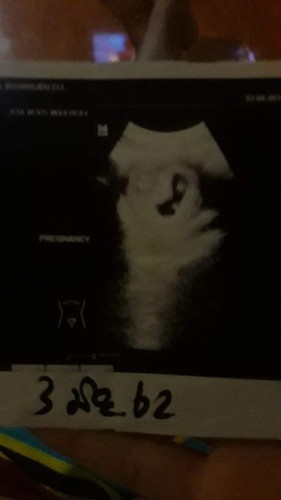

มีจุดขาวๆสองจุดเเบบนี้ใช้แฝดไหม่ค่ะ??

อาจจะแฝดค่ะ รออีก 3-4วีคไปซาวอีกทีดีกว่าค่ะ เพื่อความชัวร์ ถ้าแฝดจะเป็นแฝดแท้ เพศจะเหมือนกันทั้งสองคนค่ะ หญิงหญิง หรือ ชายชาย ค่ะ. เพราะตามรูปซ่วของแม่ เห็นจุดขาวๆ 2จุด อยู่ในถุงน้ำคล่ำเดียวกันค่ะ

ถ้าเปนครรภ์แฝดจะมีถุงตั้งครรภ์2ถุงจร้า ถ้าแฝดที่อยู่ถุงเดียวกันจะอันตรายมากค่ะแม่ ของไห้เปนแฝดนะค่ะ บ้านนี้ก้แฝดจร้า

คุณหมอบอกแฝดเหรอคะแม่เราดูไม่เป็นอ่ะของเราตอนซาวด์5เดือนเพื่อดูเพศถึงรู้ว่าตัวเองท้องแฝดถุงเดียวกัน

น่าจะแฝดเพศเดี๋ยวกันคะ คือ หญิงคู่ หรือชายคู่ เพราะถ้าแฝดชายหญิงจะมีถุงครรภ์2ถุง

ของเราแฝดแท้ค่ะ อยู่ในถุงน้ำคว่ำเดียวกัน ถ้าแฝดเทียมจะมีถุงน้ำคว่ำ 2 ถุงค่ะ

ถ้าแฝดจะเป็นสองถุงค่ะ ของเราซาวเจอตอนสี่เดือนอยู่คนละถุงค่ะ

ของเราท้องแฝด แบบแฝดเทียม คนละถุงค่ะ จะเห็นแบบนี้ ตอน 5week